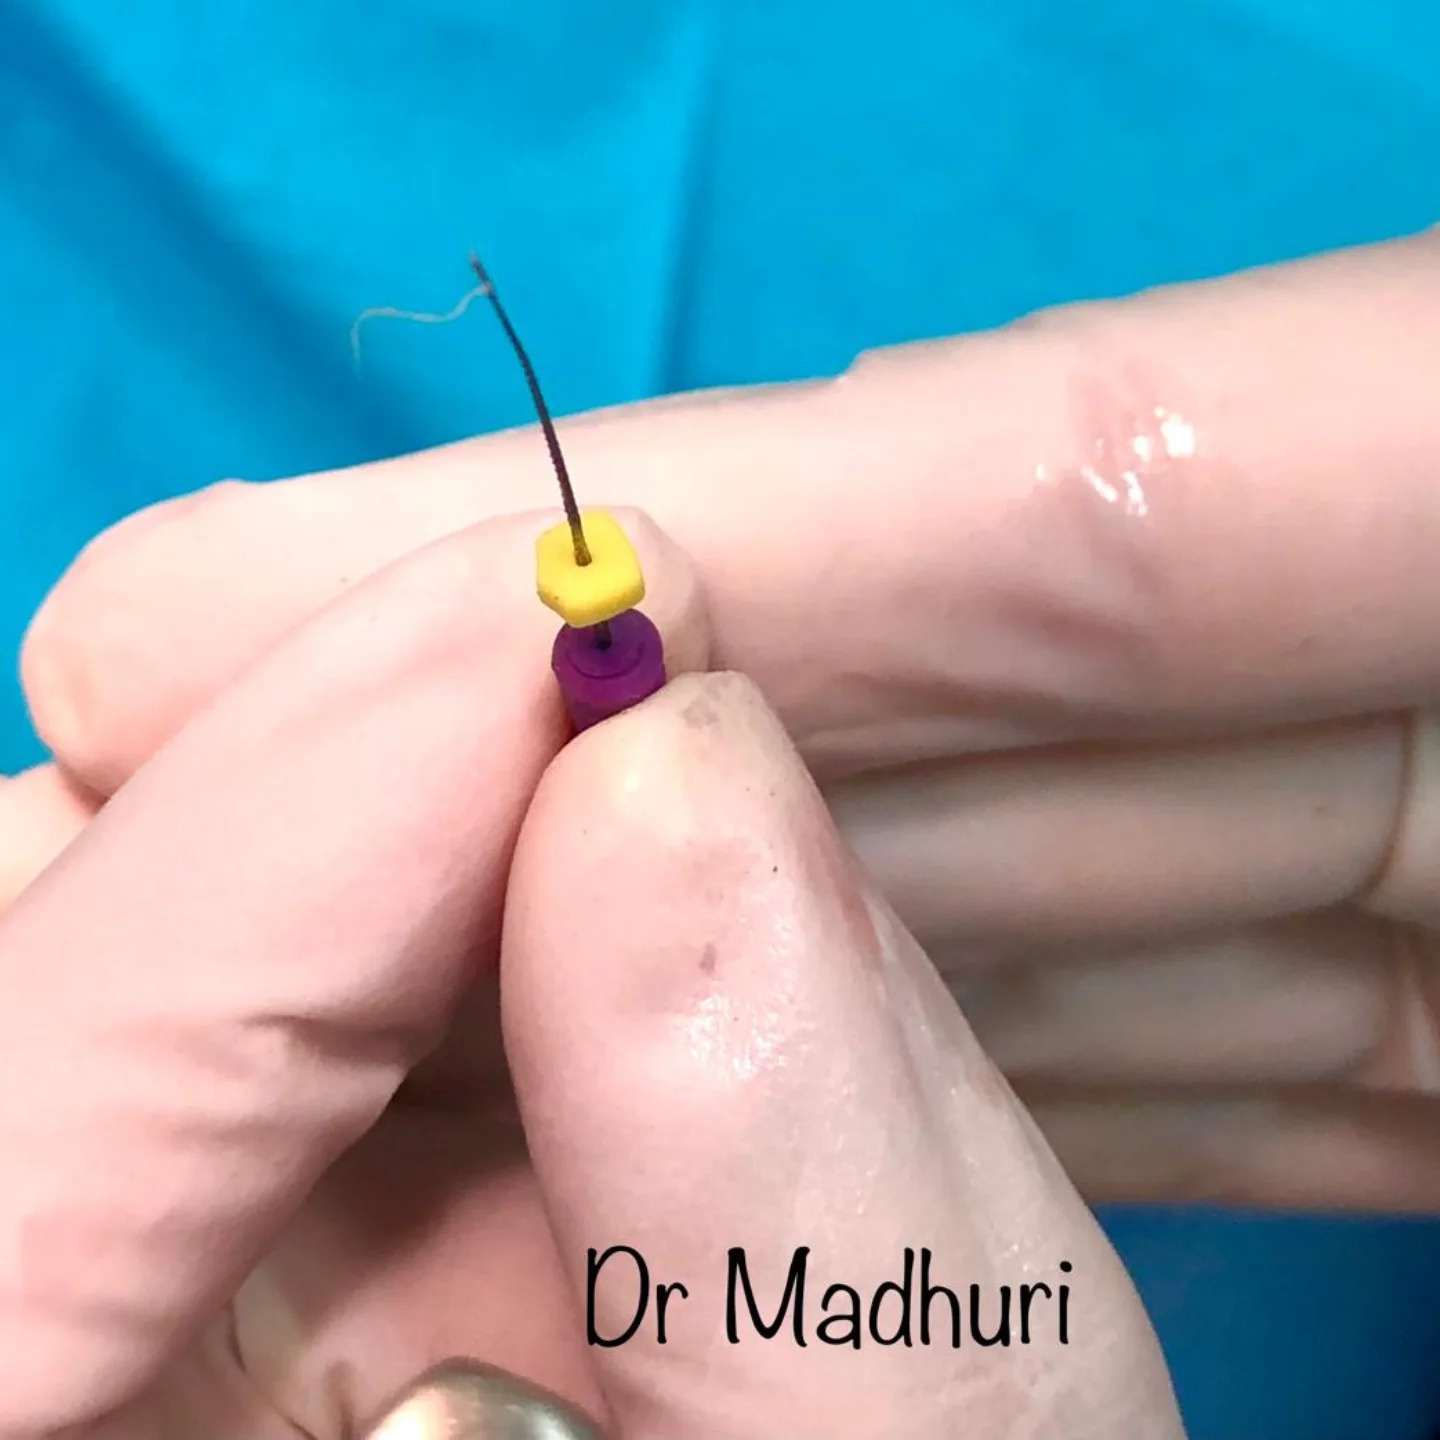

Explore Our Clinical Dental Gallery

Welcome to our official treatment gallery, showcasing the real results, smile transformations, and advanced dental care delivered by Dr. Madhuri. We believe that a picture is worth a thousand words when it comes to the art and precision of modern dentistry. Review our comprehensive visual portfolio below to see how our dedicated care helps patients achieve healthy, beautiful, and confident smiles.